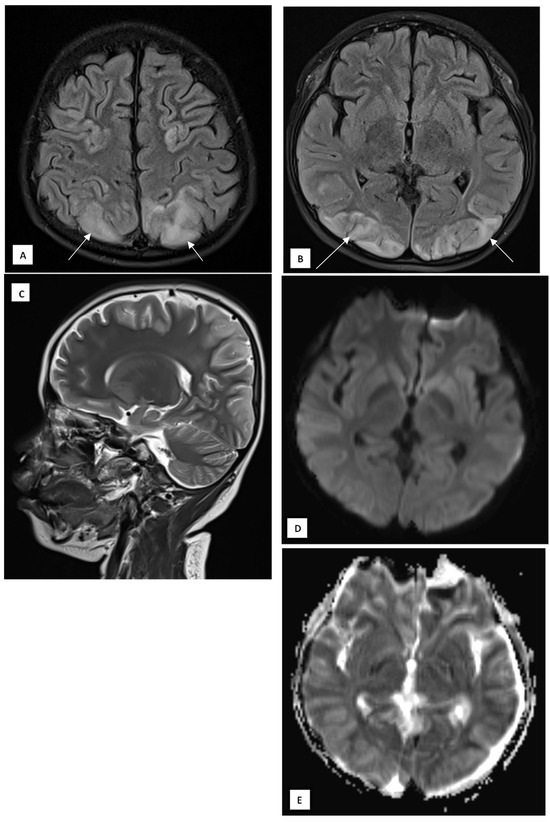

Posterior Reversible Encephalopathy Syndrome as an Under-Recognized Neurological Complication of Multisystem Inflammatory Syndrome in Children: A Case from Indonesia

Posterior Reversible Encephalopathy Syndrome (PRES) is a rare but potentially reversible neurological manifestation associated with Multisystem Inflammatory Syndrome in Children (MIS-C). We report an eight-year-old boy who developed PRES secondary to MIS-C following asymptomatic SARS-CoV-2 exposure. The patient presented with fever, seizures, decreased consciousness, and visual disturbances. MRI revealed characteristic bilateral parieto-occipital and posterior temporal cortical–subcortical hyperintensities, while CT scans were normal. The patient achieved full neurological recovery with corticosteroid therapy, blood pressure control, and supportive management. This case underscores the importance of early MRI in detecting PRES when clinical or CT findings are inconclusive, emphasizing the need for heightened awareness among pediatric clinicians to prevent irreversible neurological sequelae. Full article